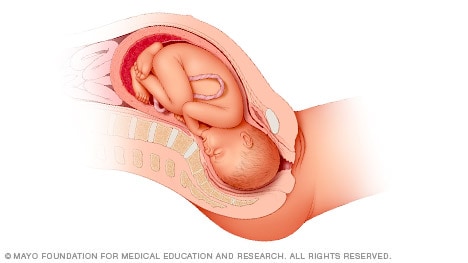

Head down, face up

When a baby is head down, face up, the medical term for it is the cephalic occiput posterior position. In this position, it might be harder for a baby’s head to go under the pubic bone during delivery. That can make labor take longer.

Most babies who begin labor in this position eventually turn to be face down. If that doesn’t happen, and the second stage of labor is taking a long time, a member of the health care team may reach through the vagina to help the baby turn. This is called manual rotation.

In some cases, a baby can be born in the head-down, face-up position. Use of forceps or a vacuum device to help with delivery is more common when a baby is in this position than in the head-down, face-down position. In some cases, a C-section delivery may be needed.